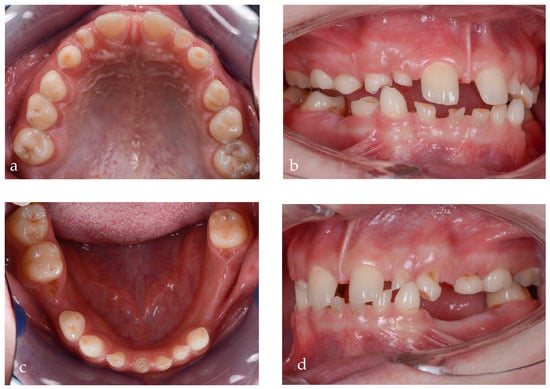

Figure 3.

Intraoral pictures of the initial clinical situation: (a) upper arch, (b) right occlusal view, (c) lower arch and (d) left lateral view.

The dental status at the time of the primary consultation was as follows: 16 with occlusal caries, 55 with occlusal caries and abraded occlusal surface, 54, 53 and 52 affected by abrasion, 11 and 21 without pathological changes, 62 and 63 abraded, 64 with occluso-distal caries and abraded occlusal surface, and 26 with old occlusal filling and secondary caries. The missing teeth in the upper arch were 12, 13, 14, 15, 17, 22, 23, 24, 25 and 27. In the lower arch, the following status was present: 36 with old occlusal filling and secondary caries, 73, 72, 71, 81, 82, 83 and 84 affected by abrasion, a residual root from 75, 85 and 46 with occlusal filling and secondary caries, and 4.7 with occlusal caries. The missing lower teeth were 41, 42, 43, 44, 45, 31, 32, 33, 34, 35 and 37 (Figure 3a–d).

From an esthetic standpoint, a low smile line, uneven gingival margins, spaces and incorrect axial inclination of the frontal teeth were present. The position of the Stomion point regarding the incisor position was acceptable.